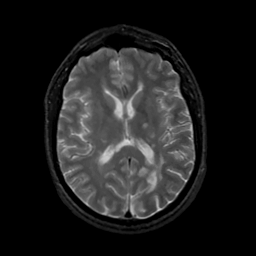

MR Study #13, May 19, 1991 -- Slice #28